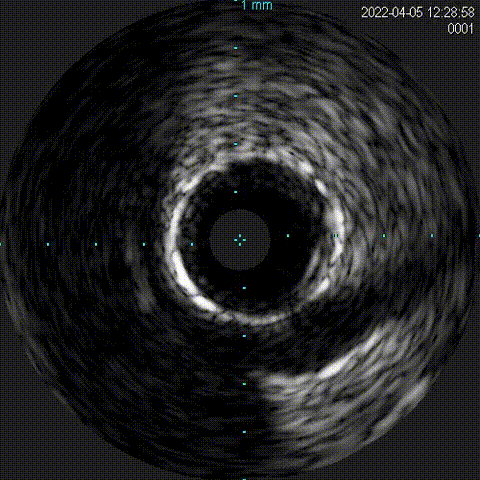

血管内超声:

导丝远端位于血管真腔,闭塞段部分内膜下走行,可见闭塞段钙化,符合术前评估结果。

支架植入:

根据血管内超声结果,在Telescope™支撑下序贯植入3.0mm、3.5mm、4.0mm支架3枚,4.0mm直径支架通过Telescope™延长管顺畅,无连接部剐蹭情况。